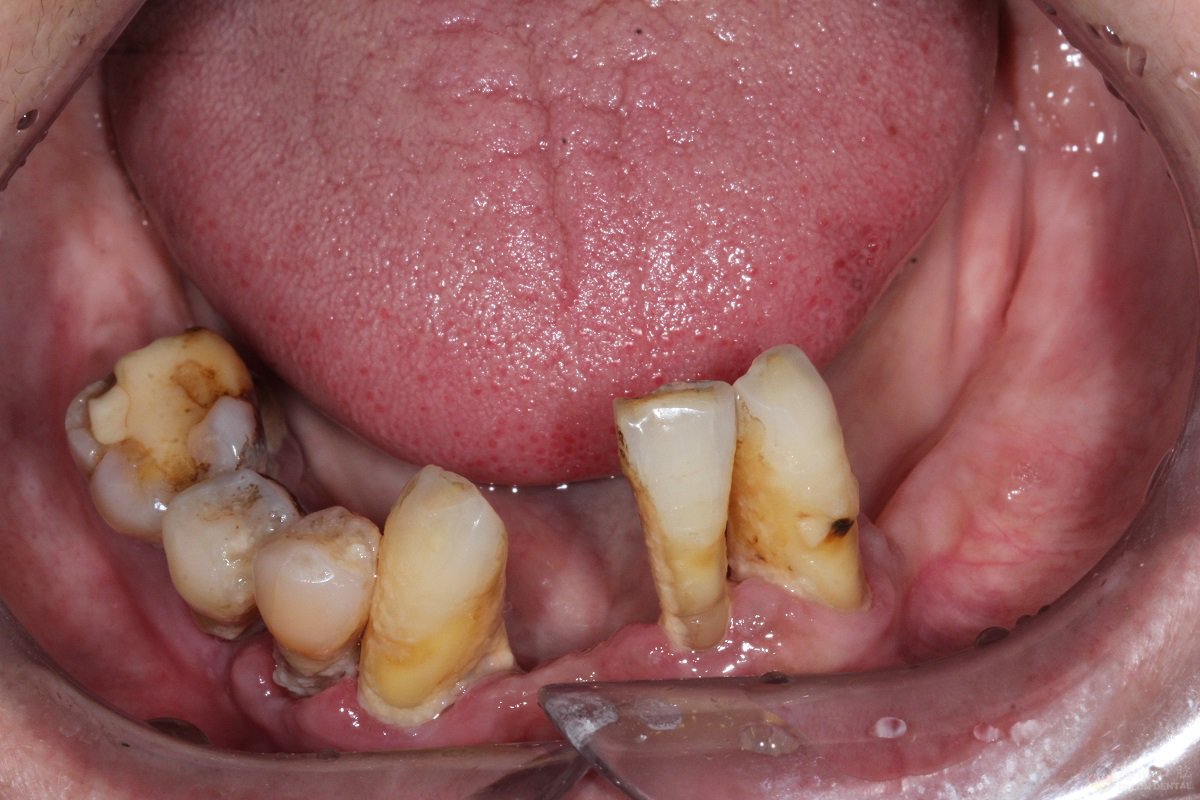

杨女士 70岁

牙齿症状:牙周炎,下颌无牙

修复方式:All—on—4即刻修复

案例经过:30岁开始陆续缺牙,期初采取活动假牙修复,后牙齿越缺越多导致无法正常饮食、睡眠,到我院时下颌只剩3颗摇摇欲坠的牙齿,拔出下颌无法保留的3颗牙后进行半口种植修复。